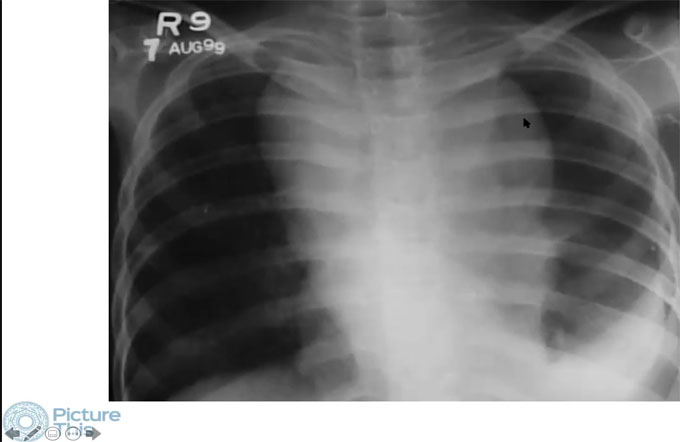

RADIOLOGY EDUCATION FOUNDATION